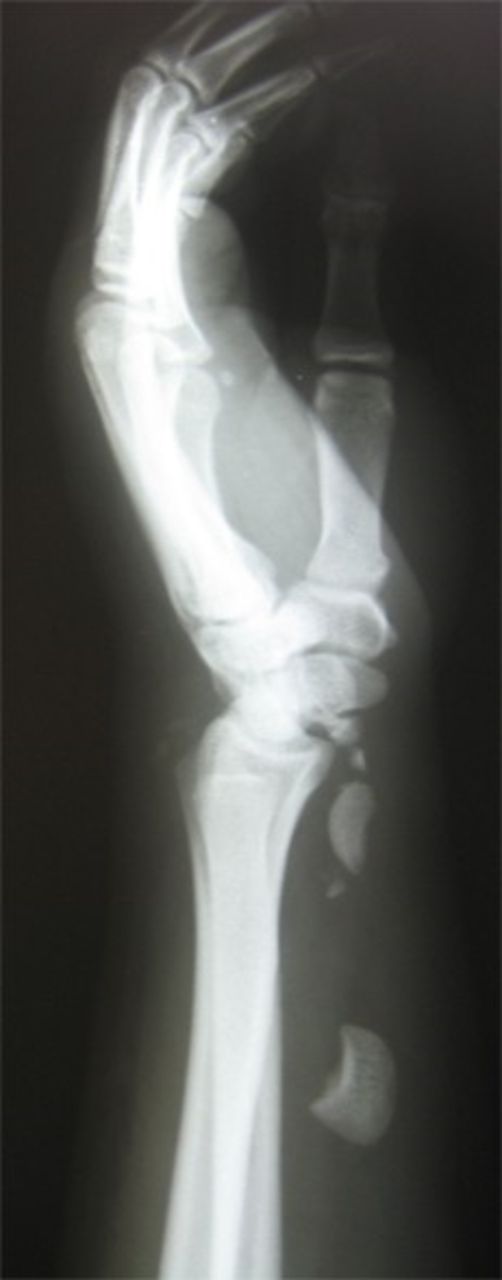

A 19-year old right hand dominant worker man presented after falling from height of about 6 meters onto his left hyperextened wrist. He was a multiple-injured case with closed fractures of femoral shaft and proximal phalanx of left second finger. In exam, wrist swelling was generally moderate with subtle deformity and ecchymosis in volar part. Range of wrist motion was very tender. A thorough serial neurovascular examination showed progressive paresthesia in median nerve territory checked by two points discrimination. Taken X-ray disclosed trans-scaphoid dorsal perilunate fracture dislocation and avulsion fracture of ulnar styloid. Excessive displacement of the lunate to middle third of the forearm and proximal scaphoid with multiple bony fragments to distal third was obvious (Figure 1a & 1b).

Posteroanterior and lateral X-rays of left wrist show perilunate fracture dislocation with excessive proximal displacement of lunate and proximal scaphoid. Loss of carpal height with broken Gilula’s arcs is obvious.